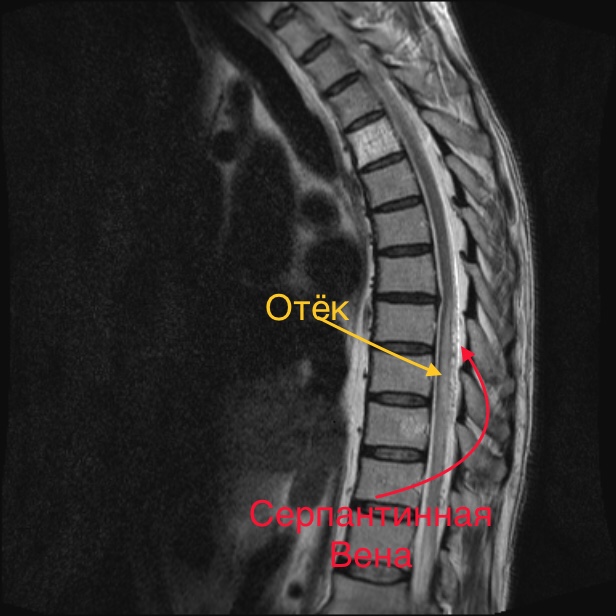

В Центре Алмазова врачи отделения нейрохирургии № 6 сразу обратили внимание на наличие у пациента двух характерных признаков: диффузного многоуровневого отека спинного мозга и серпантинной вены, что указывало на совершенно другой диагноз — спинальную дуральную артериовенозную фистулу.

Это достаточно редкая патология, при которой в определенный момент по непонятным причинам в позвоночнике открывается патологический сосудистый микрошунт — сообщение, из-за которого артериальная кровь напрямую поступает в вену, осуществлявшую отток от спинного мозга. Из-за этого спинной мозг переполняется кровью, отекает, что вызывает постепенное нарушение функции нижних конечностей.